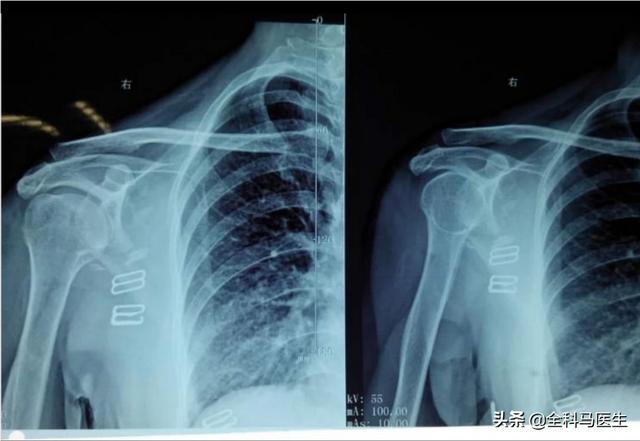

●頚椎椎間板ヘルニア.頸椎の椎間板ヘルニアが神経を圧迫すると、肩の後ろ側、特に背中の痛みを誘発することがある。頸部神経根の圧迫 6-7肩甲骨周辺が痛むこともある。

2、頸椎症、多くの人の頸椎症は背中の肩甲骨の痛みにつながる、肩甲骨の神経のほとんどは頸椎から出されているため、頸椎の局所的な神経の圧迫や炎症が痛みを引き起こす。

もう一度、頚椎症、頚椎椎間板ヘルニアによる神経圧迫があるかもしれません、この時は肩甲骨の痛みを引き起こすかもしれませんが、この痛みはしばしば後期には遠くに放射され、首の不快感の発生のいくつかを伴うでしょう、そしてそれは徐々に悪化し、良くなる特別な傾向はありません。このような場合は、すぐに病院に行って治療を受ける必要があります。